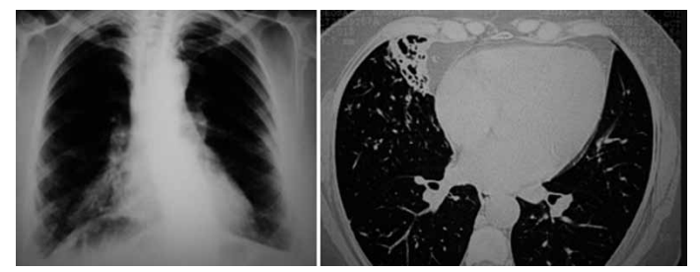

Paciente 37 anos, masculino, com queixa de tosse crônica, expectoração esbranquiçada e diversos episódios

de pneumonias que foram tratadas com antibiótico nos

últimos 5 anos. Refere ter feito investigação para tuberculose, inclusive com “endoscopia dos pulmões”, que

resultou negativa. Apresenta radiografia e tomografia de

tórax recentes a seguir: